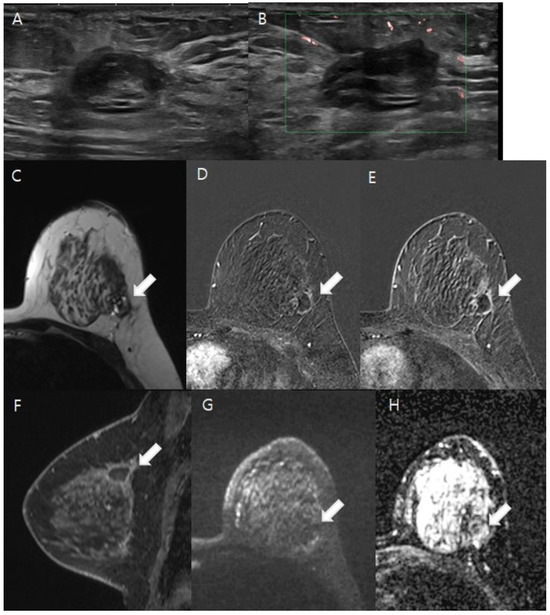

2.5. Mammography/Ultrasound Interpretation

3.2. Image Analysis Results

3.3. The Diagnostic Performance of the Imaging Modalities